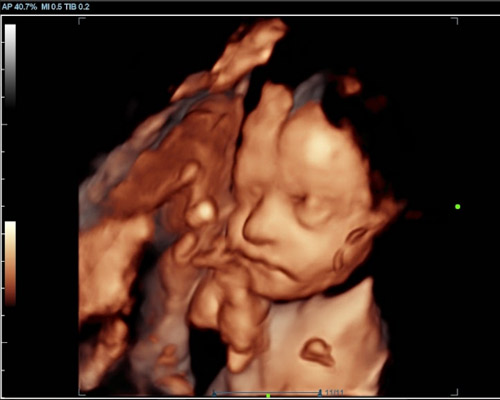

A 3D scan creates detailed still images showing your baby’s features, while a 4D baby scan allows you to see those images in motion. You may notice gentle movements, stretches, or even small expressions, which can make the experience feel much more real.

With a 4D baby ultrasound Huddersfield, this advanced imaging allows parents to see their baby in a way that feels closer to a photograph than a traditional scan.

Our Scans